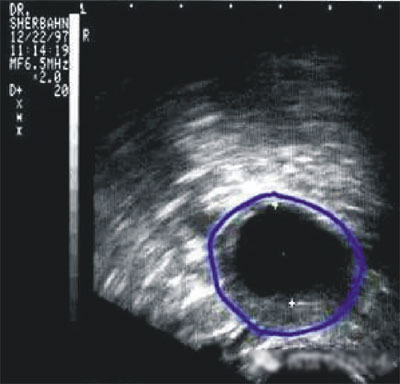

第三步:排卵監(jiān)測(cè)

常用的監(jiān)測(cè)排卵方法有基礎(chǔ)體溫測(cè)定(BBT)、陰道B超監(jiān)測(cè)排卵、血清性激素測(cè)定等。

(圖:排卵監(jiān)測(cè))

陰道B型超聲動(dòng)態(tài)監(jiān)測(cè)卵泡的發(fā)育及排卵,是監(jiān)測(cè)排卵最準(zhǔn)確可靠的方法。通過陰道B超檢查可以了解子宮及雙側(cè)附件(卵巢和輸卵管)區(qū)的基本情況,測(cè)定卵巢內(nèi)的竇卵泡計(jì)數(shù),評(píng)估卵巢儲(chǔ)備功能,動(dòng)態(tài)監(jiān)測(cè)排卵。